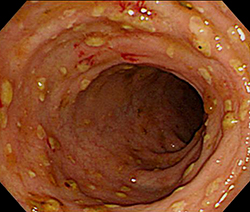

장염에 좋은 음식 10가지에 대하여 살펴보겠습니다. 장염은 위장 내키티스로서, 장의 염증으로 말미암아 설사, 복통, 구토 등 각종 증상을 같이할 수 있는 질병이고요. 장염을 앓고 있는 인간에게는 공정한 식단 절제가 굉장히 주요합니다.